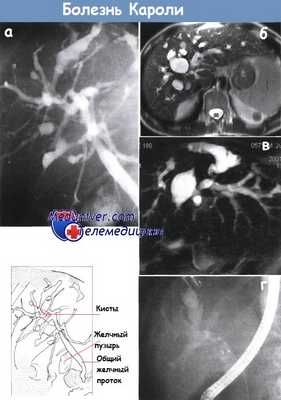

а - Эндоскопическая ретроградная холангиография. Болезнь Кароли — множественные кисты внутрипеченочных желчных протоков.

б - Множество расширенных внутрипеченочных желчных протоков. МРТ.

в - Магнитно-резонансная холангиография у того же пациента, что и на рис. а, подтвердила расширение желчных протоков.

г - Камень желчного протока, образовавшийся на фоне синдрома Кароли. Эндоскопическая ретроградная холангиопанкреатография.